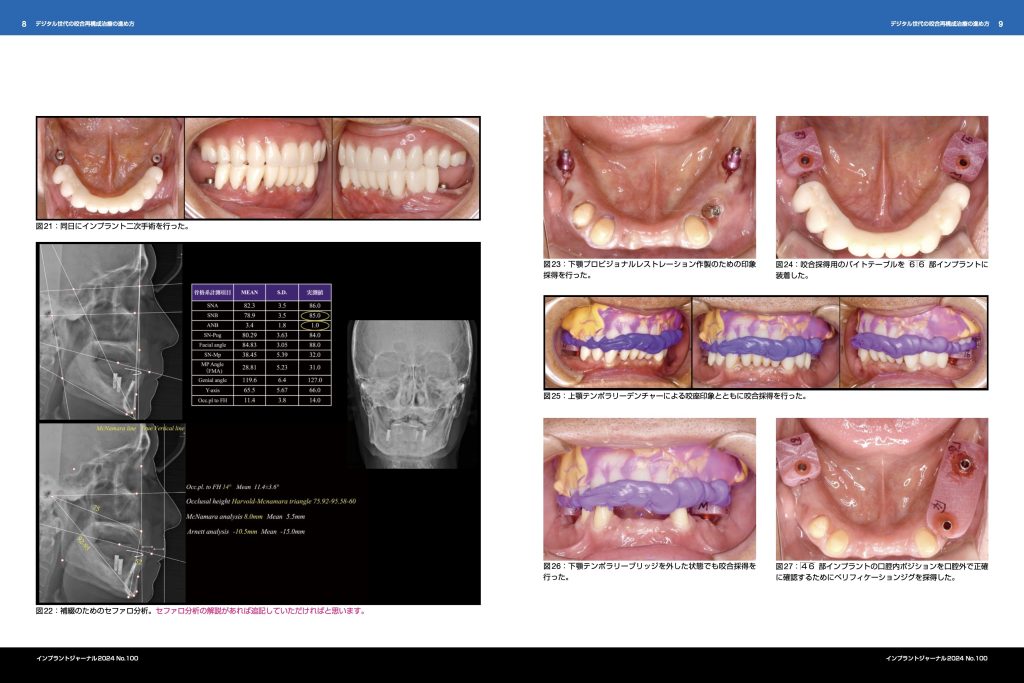

歯科専門雑誌への論文掲載 ksika_master 2024年10月22日 医院情報 0 コメント この度、歯科専門雑誌に論文を提出し、掲載許可がおりました。 「デジタル世代の咬合再構成治療の進め方」というタイトルで論文を掲載していただきます。 今後も歯科医学に貢献しながら、通院していただく患者さんにクオリティー高い治療をご提供いたします。 投稿ナビゲーション 前 過去の投稿: 10月18日(金)診療時間のお知らせ次へ 次の投稿: 10月23日(水)診療時間のお知らせ コメントを残す コメントをキャンセルメールアドレスが公開されることはありません。 * が付いている欄は必須項目ですコメント 名前 * メール * サイト